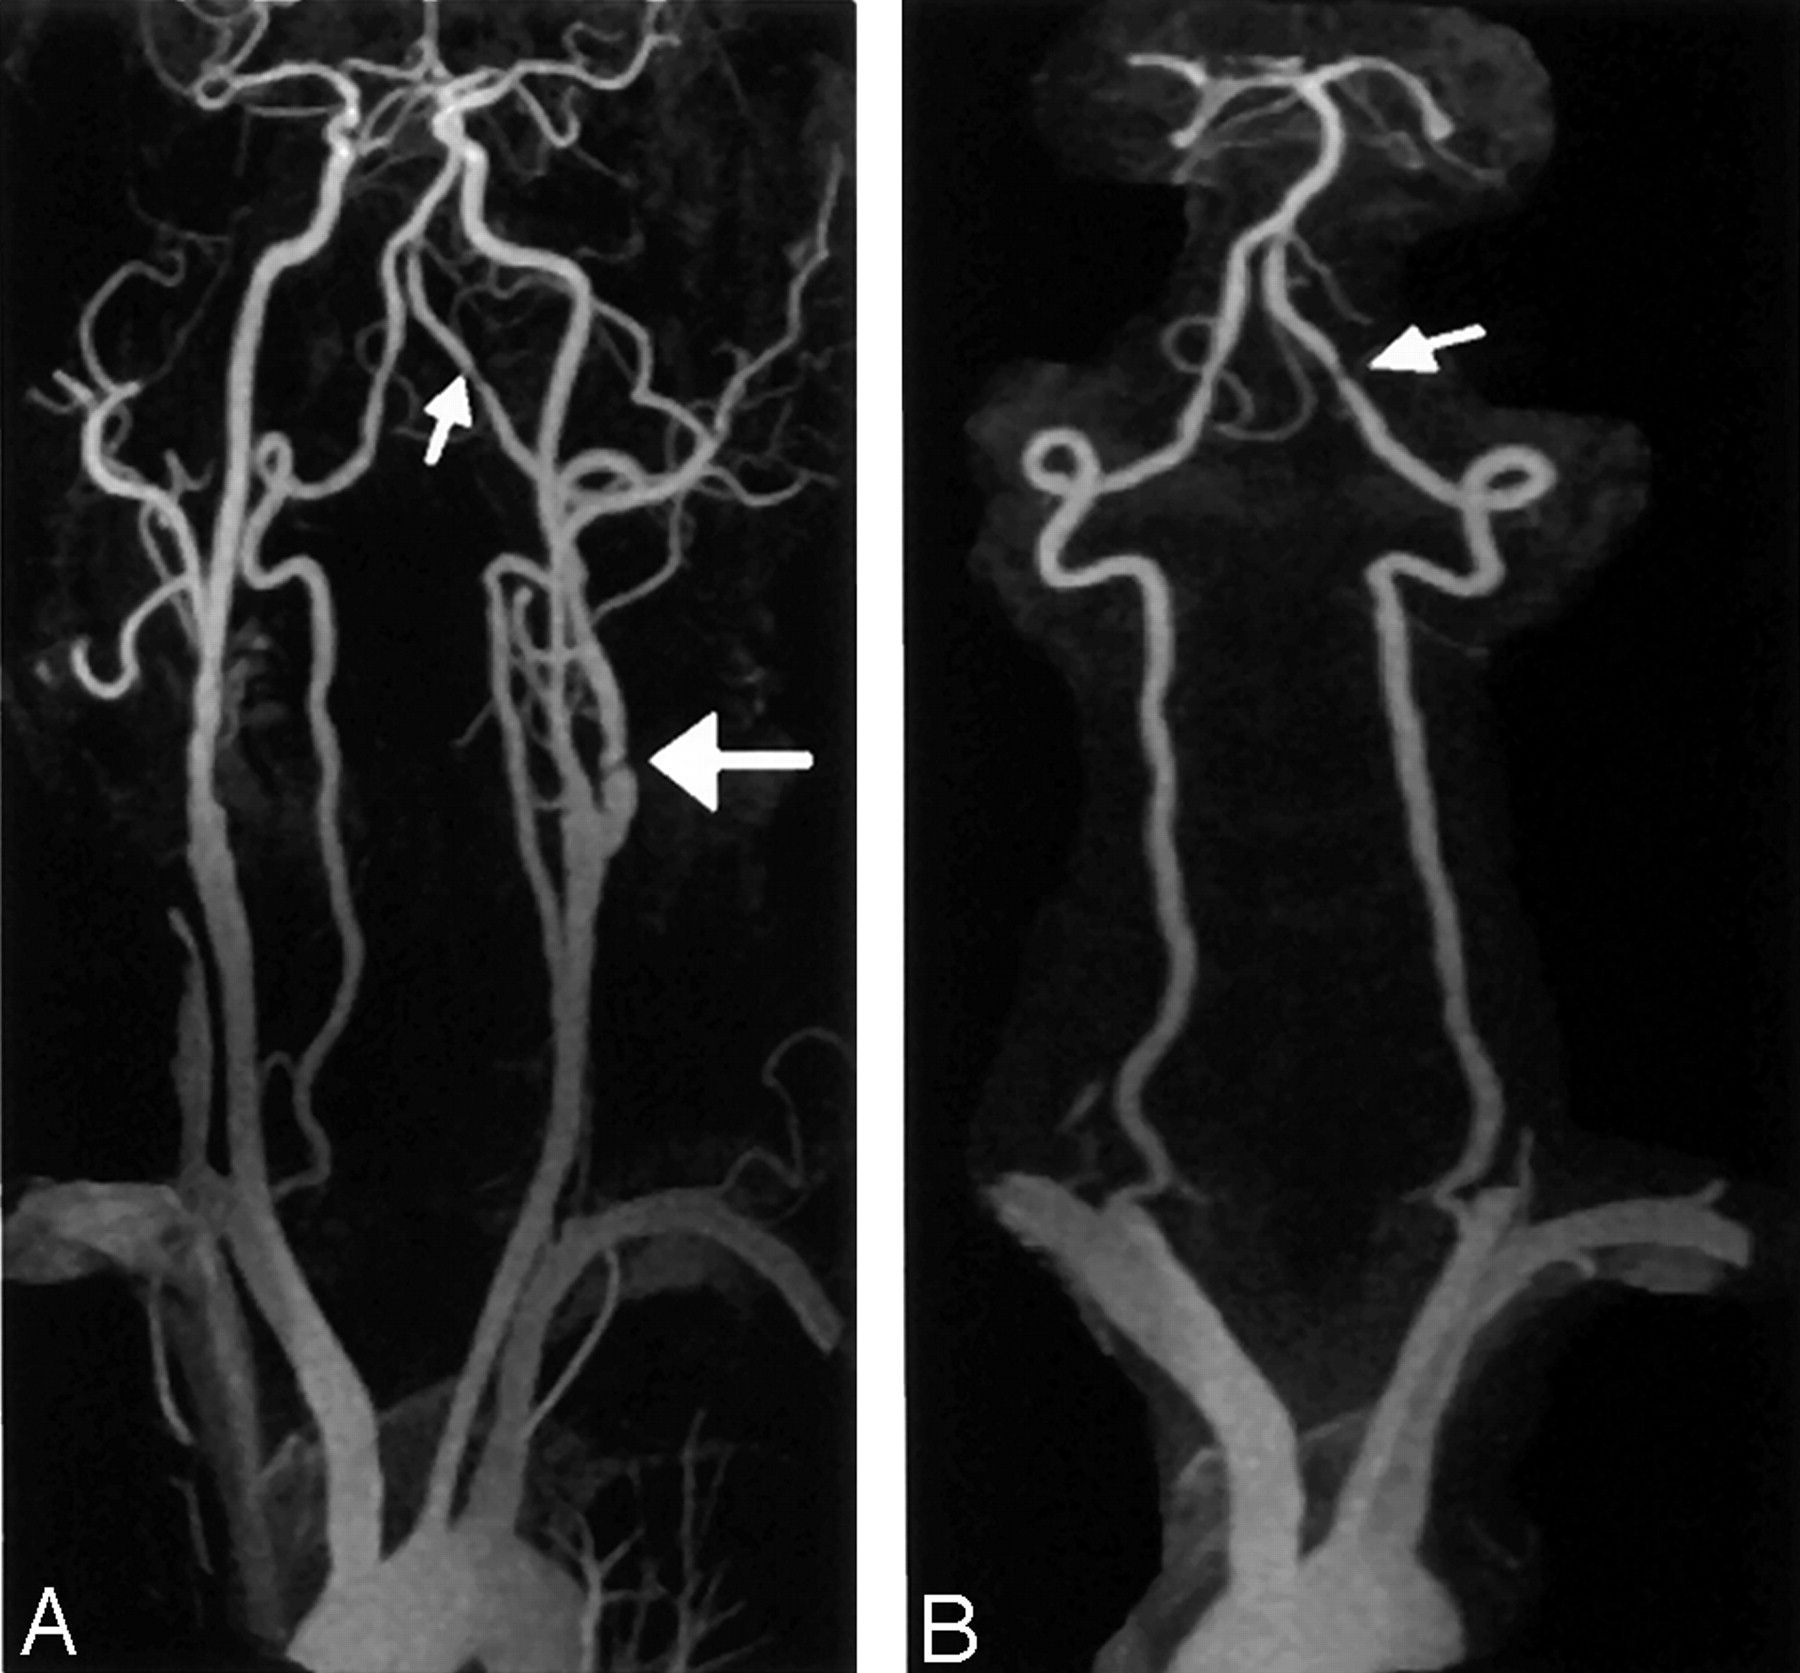

Struggling with disk disease neck? Discover the causes, common symptoms, and effective treatment options for cervical degenerative disc disease. From non-surgical pain relief techniques and physical therapy exercises to advanced medical interventions, learn how to manage neck pain, restore mobility, and improve your quality of life with our comprehensive guide to spinal health and cervical spine recovery.